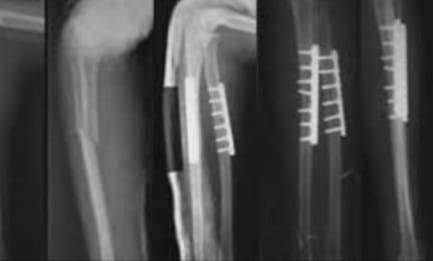

The Veer Hospital provides effective and high-quality healthcare services with 20+ departments, 16 special units and 50+ physicians. We offer an up-to-date medical approach in an ethical and reliable environment. We maintain our reputation in the health sector with our experienced medical staff who continuously improve qualified healthcare with an uncompromising focus when it comes to proficiency and academic values.